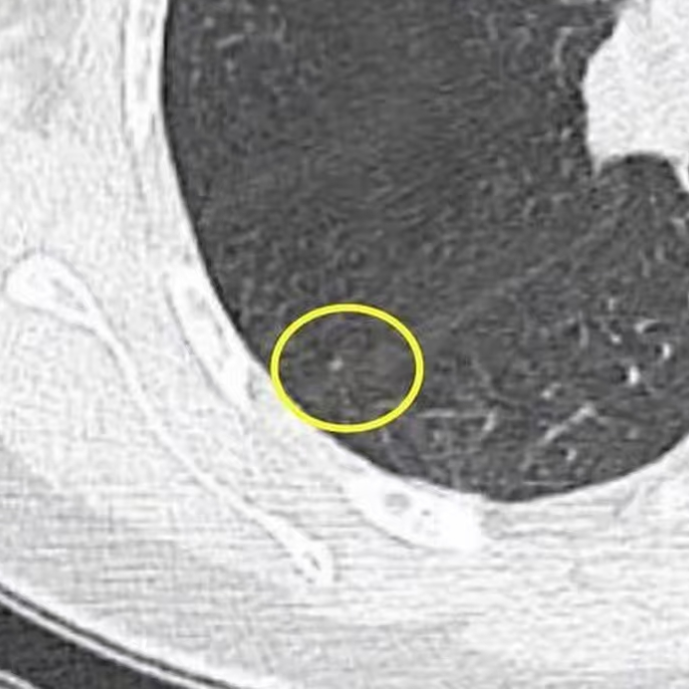

健康直通车: 健康是生命的宝贵财富,也是幸福生活的基石。为了更好地服务广大百姓,传播健康知识,葫芦岛市第二人民医院推出“健康直通车”专题栏目,将专业的医学知识以通俗易懂的方式传递给每一位市民,掌握科学的疾病预防方法,共同构筑健康中国的坚实基石。 什么是肺结节 肺结节是指肺内直径小于或等于3cm的类圆形或不规则形病灶,影像学表现为密度增高的阴影。大于3cm的称肿块。肺结节依其密度不同可分为实性结节、部分实性结节、磨玻璃结节,其中部分实性结节的恶性可能性最大,磨玻璃结节次之,实性结节尤其是小的实性结节结节最可能是良性的。 肺结节的常见病因 1、良性(约90%) 🔸 感染:结核、真菌、细菌性肺炎后遗留的瘢痕; 🔸 非感染:错构瘤(良性肿瘤)、炎性假瘤、血管瘤等。 2、恶性(约10%) 🔸原发性肺癌(如腺癌、鳞癌); 🔸转移性肿瘤(其他器官癌症转移至肺)。 如何根据影像判断肺结节性质 1、依据结节大小判断 🔸小于0.5cm的肺结节绝大多数都是良性的,属于微小结节。即使部分小于0.5cm肺结节是恶性的,但是适当的观察不影响预后。每年复查一次胸部CT就可以。 🔸大于0.5cm持续存在的纯磨玻璃结节,观察6个月,若持续存在,不管有无进展均多数是恶性的,视患者意愿,手术可以立即做也可观察至进展再做,不影响预后。 🔸大于0.8cm的部分实性结节恶性可能性非常大,应积极评估结节边缘毛刺、分叶、胸膜凹陷等征象。 🔸若实性部分大于0.5cm,恶性率显著提高。若在3~6个月随访期间实性部分增大或者总体部分增大,都可以考虑手术切除。而即使小于0.8cm的部分实性结节也需3个月就复查对比。 2、依据肺结节形态 如CT上提示病灶形态不规则、毛刺、分叶、胸膜凹陷、空泡征、血管集束征等,符合恶性肿瘤的征象。 🔸结节与正常肺组织之间界限非常清楚的恶性可能性大。 🔸结节密度不均呈混杂密度或均匀较大纯磨玻璃结节也基本是恶性的。 🔸有胸膜牵拉(不管是肺表面的脏层胸膜还是叶间裂部位的胸膜)的恶性可能性大。 🔸结节有浅分叶、细毛刺,密度较高而与周围肺组织边界不清的恶性可能性大。 🔸磨玻璃或混合磨玻璃结节存在小空洞的恶性可能性大。 🔸影像上似慢性炎表现,而没有炎症相关的其他异常,特别当所谓炎症区域内部或一侧与正常肺组织之间界限非常清楚的基本上是恶性的。 3、从结节发展情况来看 所有随访中增大进展的都需要考虑恶性可能,不进展而持续存在的纯磨玻璃结节也需考虑恶性。 葫芦岛市第二人民医院肺结节诊治中心孙振教授深耕肺结节领域四十余载,凭借对临床实践的执着钻研与深厚积淀,在肺结节精准诊断及鉴别诊断领域形成独到见解。他系统总结海量临床病例,创新性提炼出一套科学化、规范化的肺结节全周期诊疗体系,尤其在早期微小结节的影像特征识别、良恶性风险分层等方面积累了丰富经验,为众多患者提供了精准、高效的诊疗方案。 人民医院·人民名医 孙振 主任医师 三级教授 ·葫芦岛市第二人民医院胸外科主任、肺结节诊治中心主任 ·中国医科大学客座教授 ·原央企总医院著名胸外科专家 ·辽宁省医学会胸外科委员 ·辽宁省抗癌协会肺癌专业委员会委员 ·辽宁省细胞生物学学会食管癌专业委员会理事 ·主持多项科研成果获科技成果奖、科技进步奖、国家专科奖项 医学成就 从事胸外科临床工作近40年,担任胸外科首席专家及科室主任20余年,是我省胸外科领军人物,推动肺癌、食管癌等胸部肿瘤外科的规范化诊疗,在央企总医院牵头成立了肺结节诊疗中心,率先开展CT引导下肺内小结节定位切除,既确切完整切除肺内小结节,又降低肺功能损害。 专业特色 擅长肺癌、食管癌的外科手术和综合治疗,在各类高难度胸外伤手术治疗、胸腔镜微创手术、胸腺瘤手术及复杂并发症处理方面具有高深造诣,尤其擅长肺癌早期诊断,胸部小结节CT早期肺癌的鉴别等。完成各类高难度胸外科手术5000余例,其中微创手术占比达90%,治愈率达98%,多项业务填补省内空白。 开展的高难手术 胸腔镜肺部结节微创手术、肺癌根治术、食管癌根治术、各种纵隔肿瘤切除术、胸骨后甲状腺手术及胸部复合性外伤的抢救手术等。